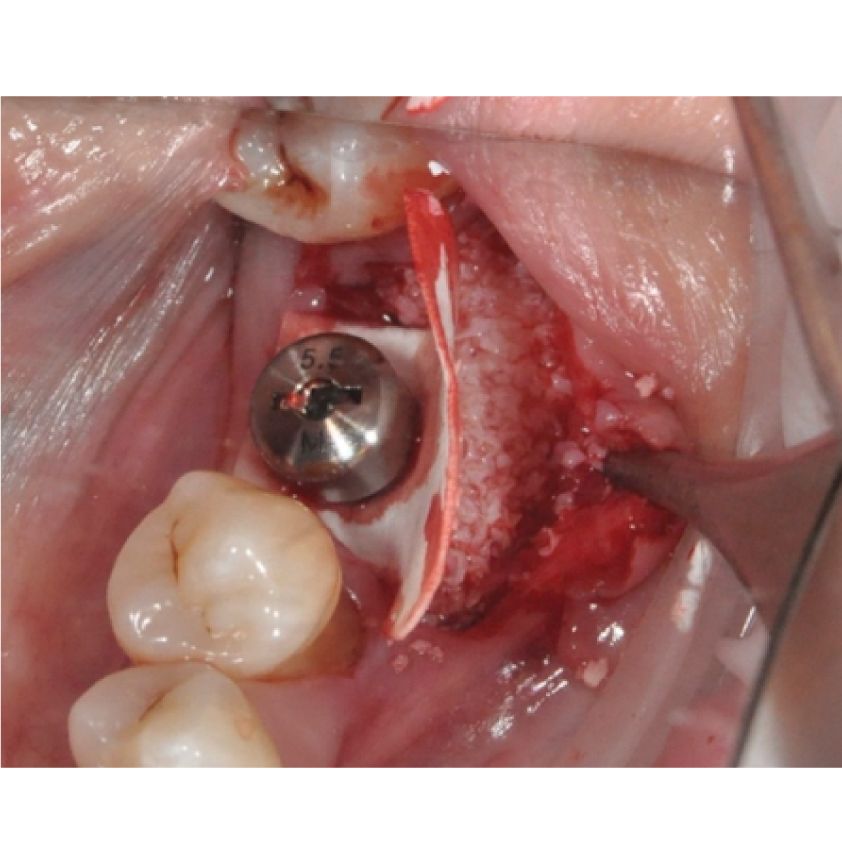

Director’s Clinical Cases

Director’s Clinical Cases